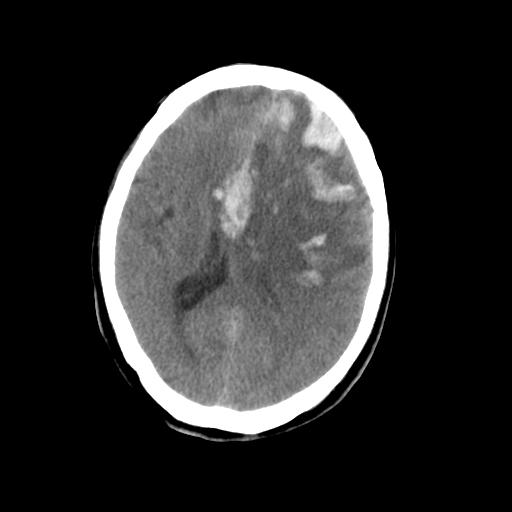

男,78岁。自诉两周前因右侧肢体障碍行ct检查,诊断为脑梗塞(患者ct片已丢失)治疗好转后出院。现因意不清12小时,又行ct检查。

结合病史考虑左侧额颞顶叶出血性脑梗塞。

结合病史考虑左侧额颞顶叶出血性脑梗塞